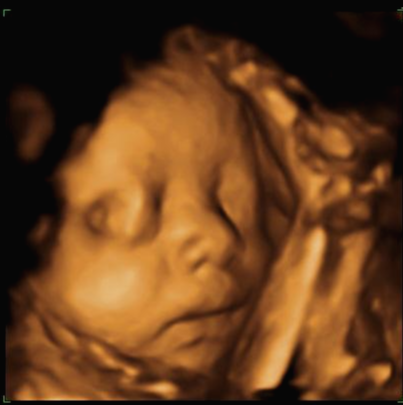

24주 차에 다시 사설로 초음파 검사를 받으러 갔는데 초음파를 보시더니 정밀 초음파 검사 때 성별 딸이 었냐 아들이 었냐 물어보시길래 딸이라고 말을 하니 미안하다고 지금 보니 딸이라고 하길래 이때는 정밀 초음파 검사 후 한 달 뒤여서 상관없다고 ㅋㅋㅋㅋㅋ 아들인지 딸인지 뭐가 중요하냐고 아이만 건강하면 된다고 하니 ㅎㅎ 그때서야 웃으시더라고요 ㅎㅎ 많이 미안했던 모양... 워낙 아이 건강상태를 꼼꼼하게 잘 봐주시고 만족할만하게 아이 얼굴 초음파 사진을 찍어주셔서 다 용서가 됐어요 ㅎㅎ

내 뱃속에 이렇게 사랑스러운 아이가 있다니 >. < 이렇게 이쁜 아이를 보면 성별반전은 중요하지 않아요~

입체 초음파 사진은 항상 만족스러워요! 사진 보면 벌써 태어난 아기처럼 어찌 이리 이목구비 뚜렷하고 아이 얼굴이 선명하게 잘 보이는지~ 제아이라 이렇게 사랑스러운 걸까요~? ㅋㅋㅋ